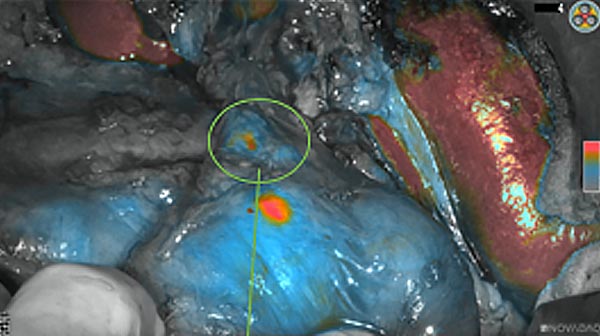

Intraoperative fluorescence imaging of the pancreas part that contains tumor

The tumor area light up fluorescently and so does a lymph node (LN; red circle) that is located on top of the tumor area. We can also see some lymphatic ducts (green circle).

After removal of the pancreas tumor fluorescence imaging was performed to check that there was no residual fluorescence left in the wound bed. A little bit of background fluorescence was found in the intestine.